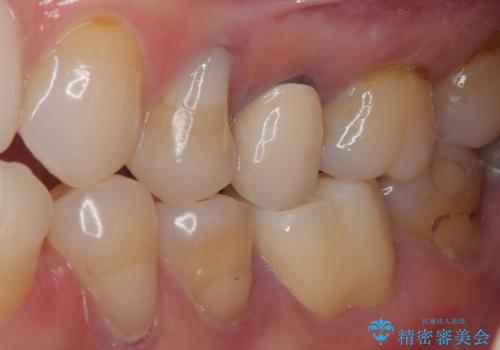

相談の上、フルジルコニアクラウンにて補綴治療を行うこととしました。

仮歯装着によりしみていた症状はおさまり、無事に治療を終えることができました。